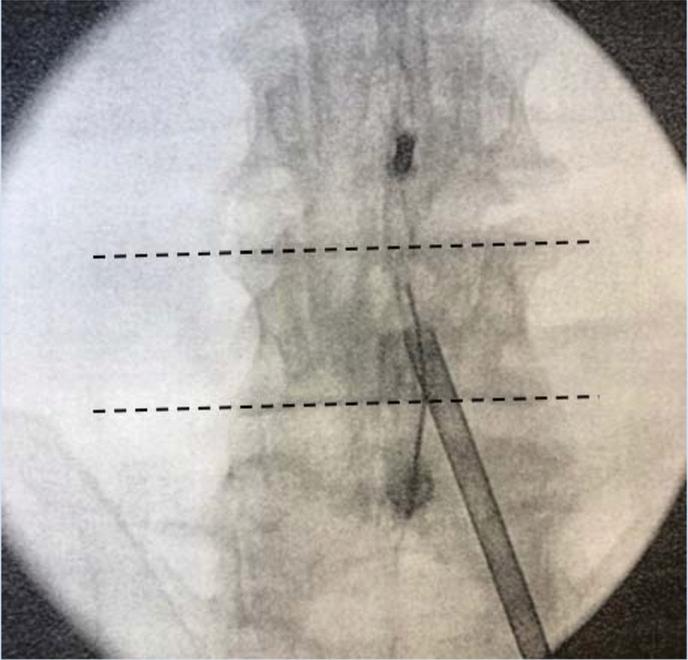

1. OperativeLevelIdentification:Identifytheoperative levelusingfluoroscopy.

PatientPositioning:Prone(thoracolumbar)forneedle placementfromeithersideandeasierpositioningofCarm Cushionstosupportheadandbody Adedicated biplanefluoroscopysuiteispreferred,butatleastone C-armunitisnecessary

Needleplacement:

Transpedicular:needlethroughfulllengthofpedicle a

Parapedicular:needlealongthelateralcortexof pedicle b

TrajectorySafetyConsiderations

APviewsafetyconsiderations;(a)keeptomedialborderof pedicleinordertoavoidspinalcord/thecalsac,(b)don’t strayawayfromwithinpedicularborders,thiswillensure safetyofnervesandnerveroots lateralviewsafetyconsiderations;(a)cannulatipshouldbe seenattheposteriorbodywallinthelateralview,(b)the aorta/inferiorvenacavacanbedamagediftheanterior vertebralbodyispenetrated,(c)penetratingtheinferior pediclewallasaresultofimpropertrajectorycancause nervedamage

Image-guidancestrategiesforatranspedicular approach:

a

b

Endontechnique:asdescribedbelowinthe kyphoplastyproceduredescription

APtechnique:craniocaudalangulationisadjusted sothattheendplatesareperpendiculartothe image.

i

Skinentrypoint1cmsuperolateraltopedicle’s centre,needleisadvancedanteriorly,medially andcaudally

iii

Needletipshouldinitiallyprojectovertheupper outercortexofthepedicle,needleisadvanced sotipprojectsovercentreofpedicleonAPand lateralviews

ii tipshouldbeoverthemedialpediclecortexas theneedlemovesacrosstheposteriorthirdof thevertebralbody.

Image-guidanceforaparapedicularapproach: Needleplacementissuperolateraltolateralpedicular cortex,entersthevertebralbodyatthejunctionofthe pedicleandvertebralbody

5. Cementplacement:fluoroscopicmonitoringis importanttoensurecementremainswithintheareaof target Lateralviewsaremoreimportantasitenables theevaluationoftheposteriorpositionofcement relativetospinalcanalandneuralforamina

AdditionalPoints

Needleshouldnotviolatethemedialcortexof pedicle

Trajectoryofneedlecannotbealteredmuchonce needlehaspassedintothepedicle

Avoidcannulacrossingmedialpedicularborder priorreachingposteriorwall(redline,Figure9A)to ensuresafetyandevendistributionofcement

Figure13:Illustrationsof vertebroplasty.

A)Preoperativeplanningofentry pointsandtrajectory(yellow: bipedicularapproach;purple: unipedicularapproach;red:medial pedicularborder),

B)Simplifiedschematicsof relevantanatomicallandmarks andangulation

C)Approximatetrajectory, D)Lateralfluoroscopicviewof cementinjection